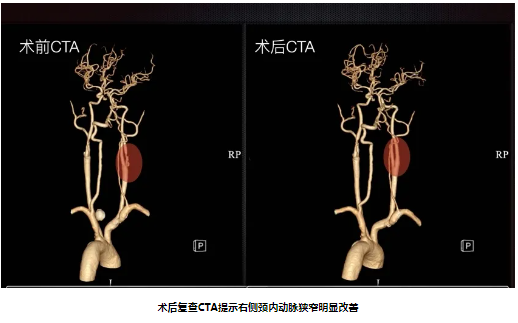

64岁男性,因“反复头晕3月”入院,既往有“脑梗死、高血压病、糖尿病”史。入院后完善颈动脉彩超及影像学检查提示:双侧颈内动脉开口重度狭窄。经颈动脉狭窄MDT团队充分讨论,结合斑块性质及患者临床需求,脑血管外科团队予患者行右侧颈动脉内膜剥脱术。术后第二天患者即能下床,术后3天复查CTA提示颈动脉狭窄得到明显改善。